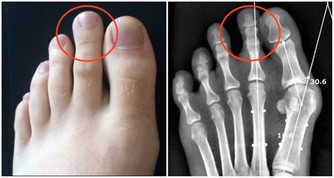

此外,維生素A還有利於為人體補充膠原蛋白。所以缺乏維生素A,就可能會使指甲出現很多凹陷或紋路;皮膚也會感到瘙癢,變得粗糙髮乾。